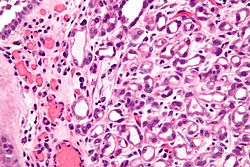

Hobnail pattern (epithelioid angiosarcoma). H&E stain. (WC/Nephron)

Hobnail pattern is a morphologic pattern that is seen in a number of contexts, including benign and malignant.

• Basement membrane area < area exposed to luminal surface.